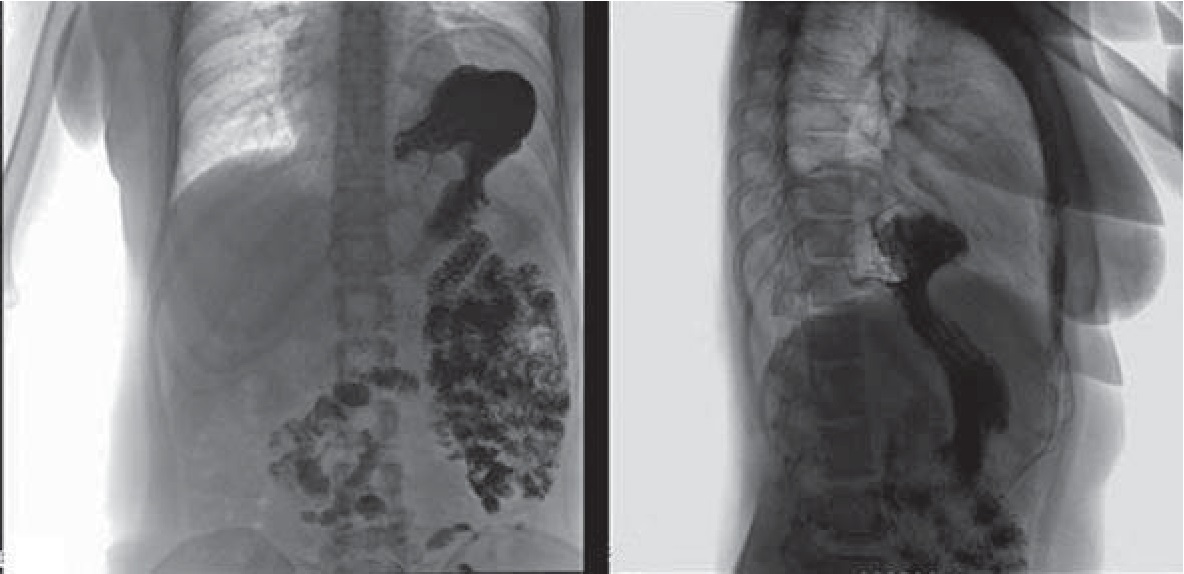

При поступлении было выполнено рентгенологическое исследование с контрастированием. На обзорной рентгенограмме органов грудной полости купол диафрагмы слева расположен высоко на уровне 4 ребра по передней подмышечной линии, гиповентиляция легочной ткани в нижних отделах; в левом поддиафрагмальном пространстве определяется широкий горизонтальный уровень жидкости. При рентгеноскопии верхних отделов желудочно-кишечного тракта с бариевой взвесью определяется пролабирование складок слизистой свода и части тела желудка в плевральную полость – рентгенологические признаки диафрагмальной грыжи (рис. 1). Фиброгастродуоденоскопия (ФГДС) позволила выявить эндоскопические признаки фиксированной кардиофундальной грыжи пищеводного отверстия диафрагмы и очаговый антральный гастрит.

Рис. 1. Рентгенологическая картина диафрагмальной грыжи у пациентки А.